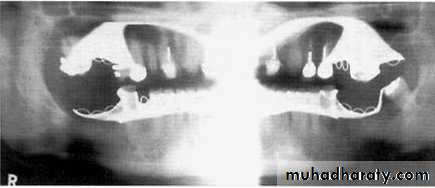

1, Mandibular condyle. 2, Articular eminence. 3, Coronoid process of mandible superimposed on zygomatic arch. 4, Posterior wall of maxillary sinus. 5, Posterior wall of zygomatic process of maxilla. 6, Hard palate. 7, Nasal septum. 8, Tip of nose. 9, Dorsum of tongue. 10, Hyoid superimposed over inferior border of mandible. 11, Inferior border of maxillary sinus. 12, Image of cervical spine. 13, Medial border of maxillary sinus. 14, Infraorbital canal. 15, Infraorbital rim. 16, Pterygomaxillary fissure. 17, Anterior border of the pterygoid plates. 18, Lateral pterygoid plate superimposed over soft palate and coronoid process of mandible. 19, Ear lobe. 20, Inferior border of mandibular canal. 21, Mental foramen. 22, Posterior wall of nasopharynx. 23, Inferior border of mandible superimposed from opposite side. 24, Soft palate over mandibular foramen of mandible.